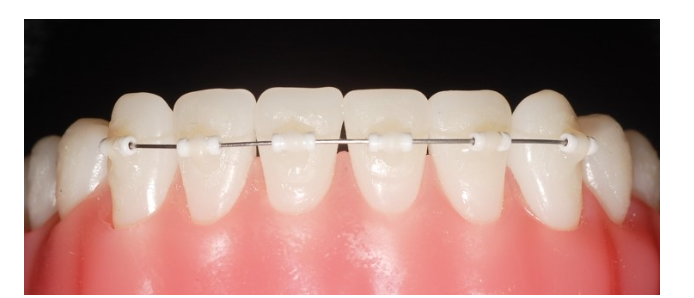

Mini Tube Appliance라고 하여

아주 작은 튜브 형태의 브라켓을 치아 표면에 부착하여

와이어를 연결하는 방식입니다.

작고 얇으며

치아 색깔과 비슷하여 티가 많이 나지 않습니다.

제일 큰 장점은 장치가 작고 얇아

큰 불편감이 없습니다.

일반적인 철사 교정에 비해서 말이죠!